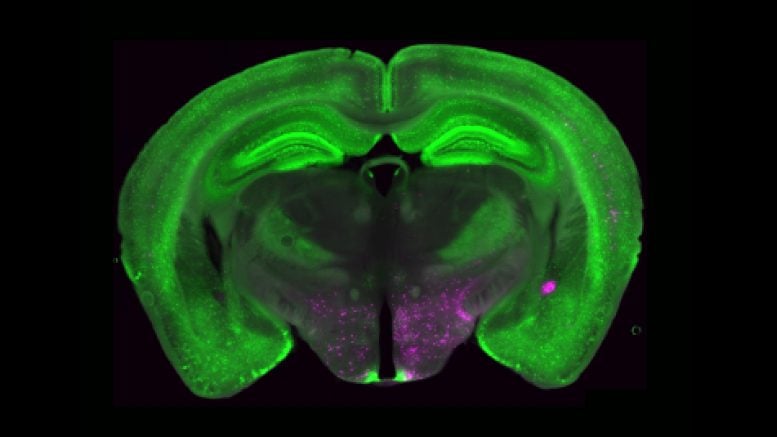

Vědci našli soubor neuronů mozků, které mohou vytočit chronickou bolest. Tyto neurony receptoru Y1 vyvažují bolest s jinými životně důležitými potřebami, jako je hlad a strach, což ukazuje, že mozek může potlačit utrpení, když je v sázce přežití. Objev by mohl transformovat, jak je chronická bolest chápána a léčena zaměřením na mozek (…)